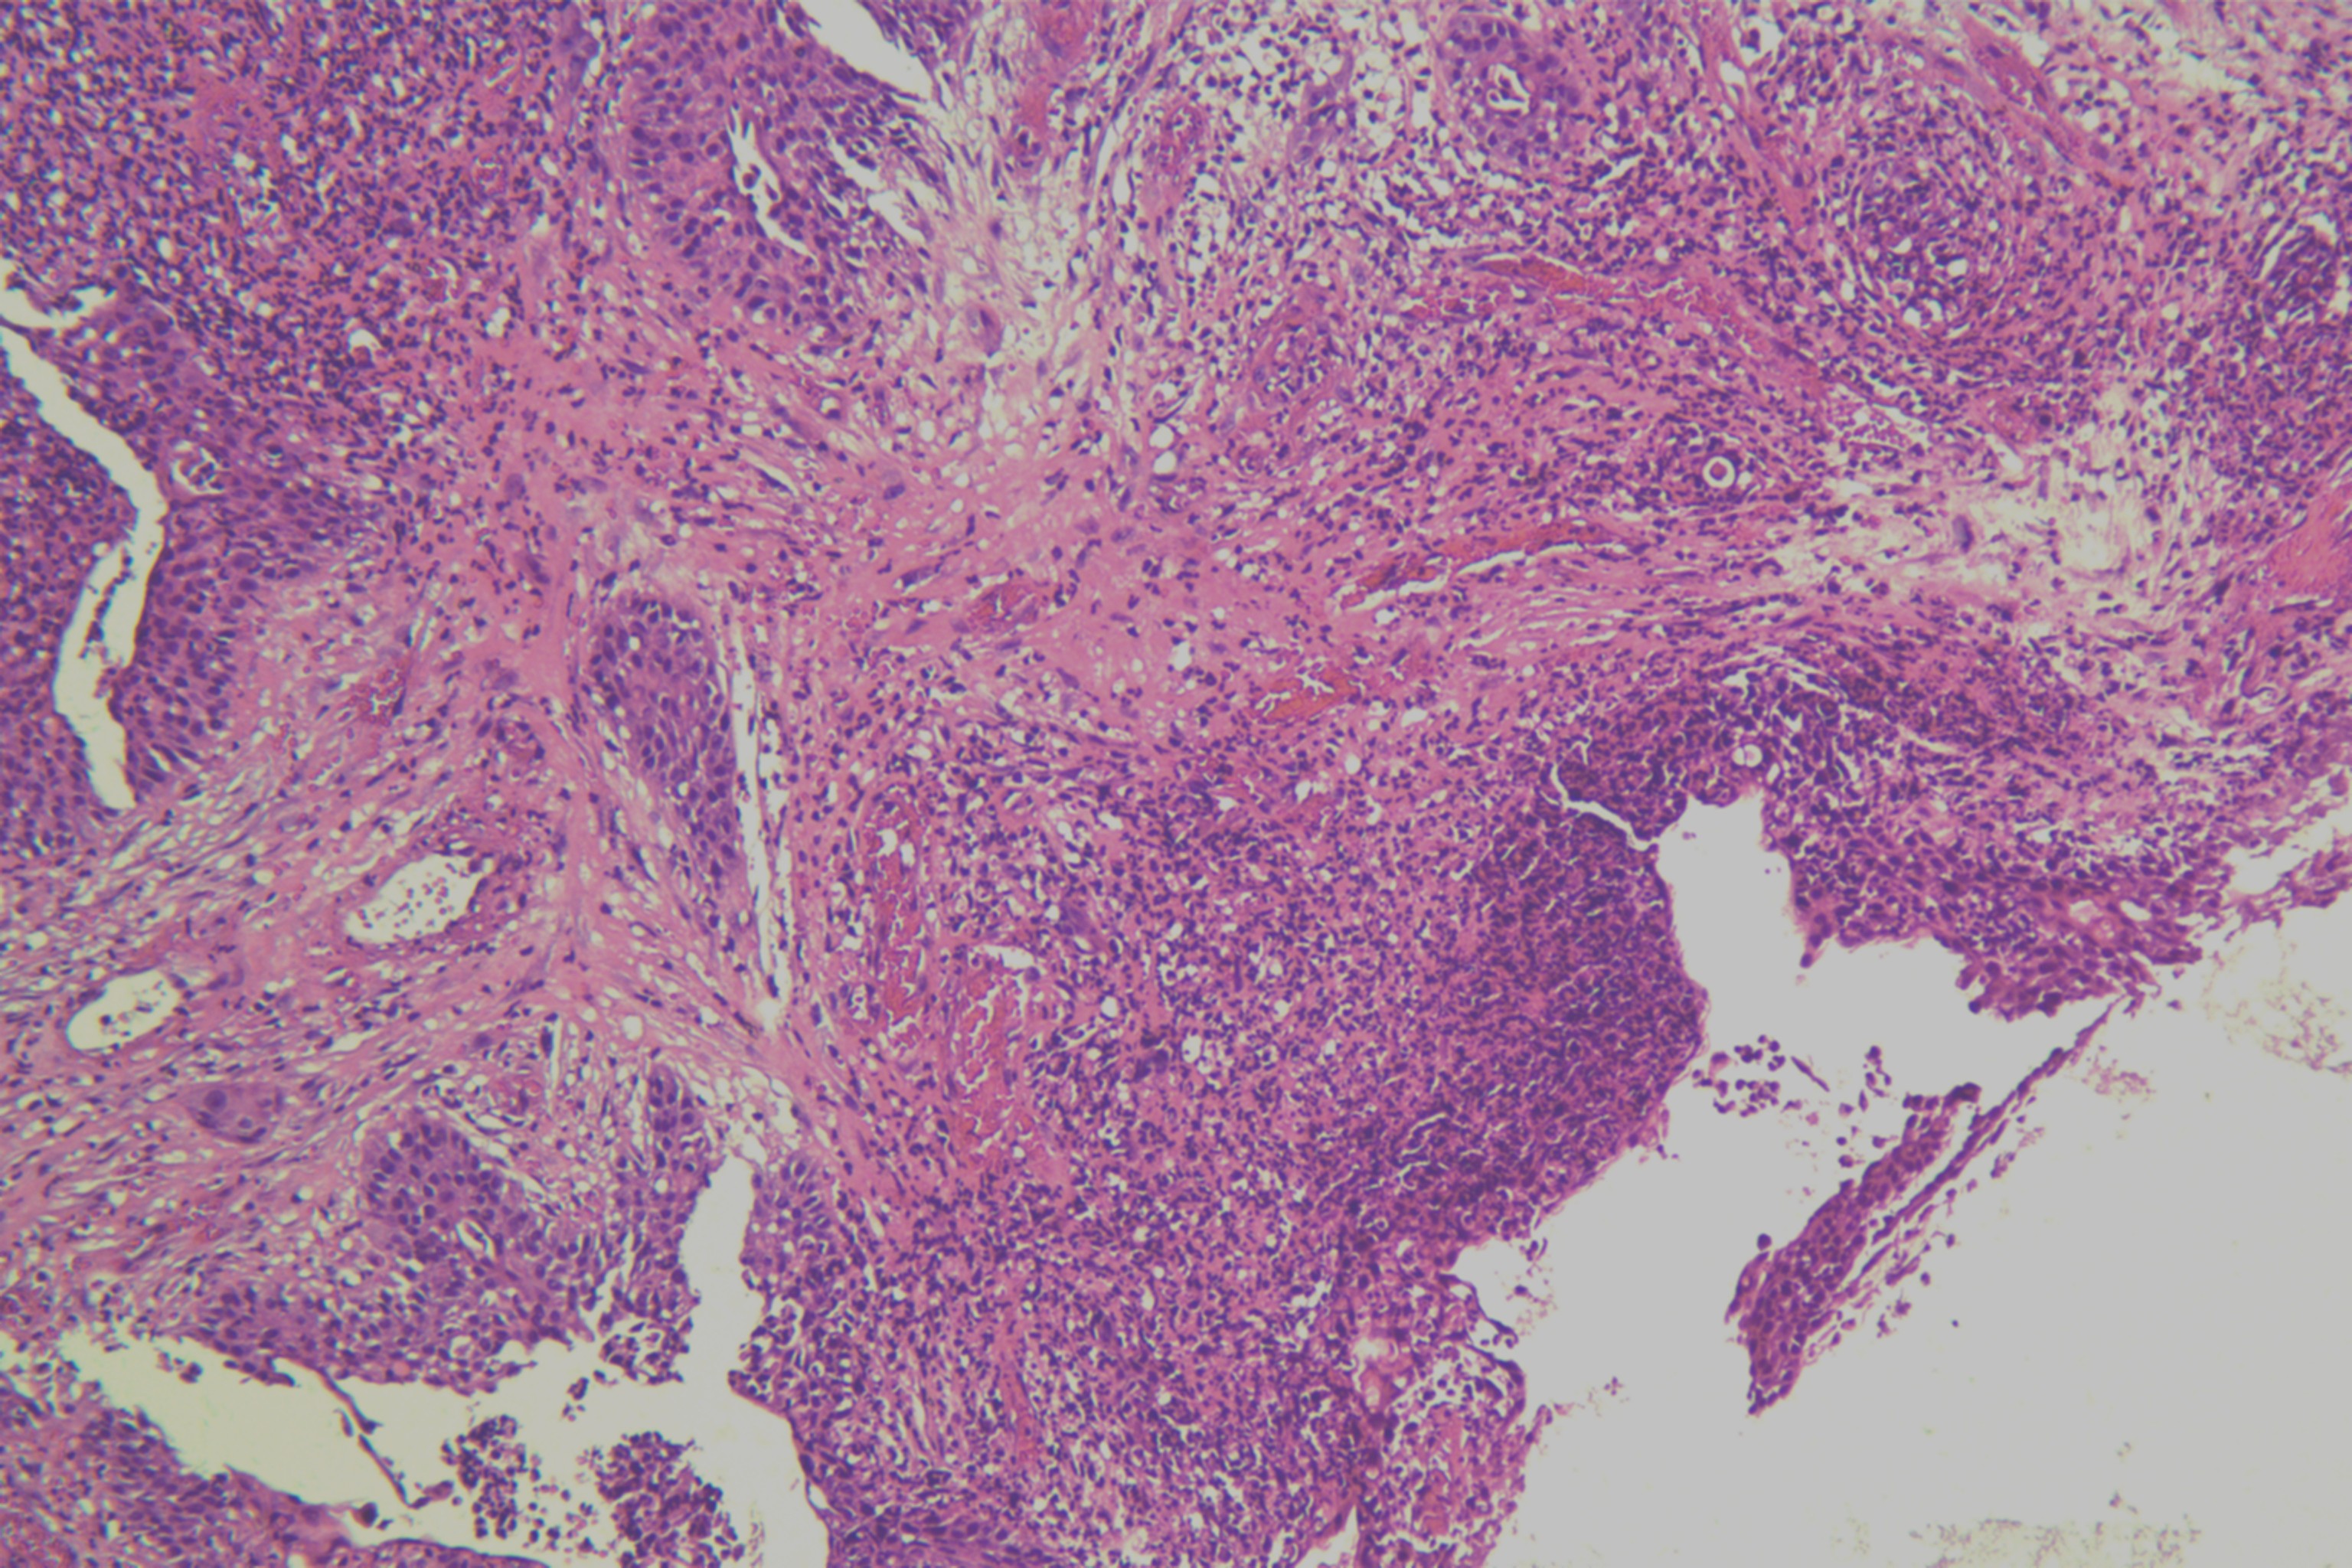

鳞癌?

性别

男

年龄

68岁

头皮肿物20年,包块逐渐增大,反复破溃

头皮肿物(局部活检)

1.5*1*0.3cm灰红碎组织一堆

考虑:基底细胞癌